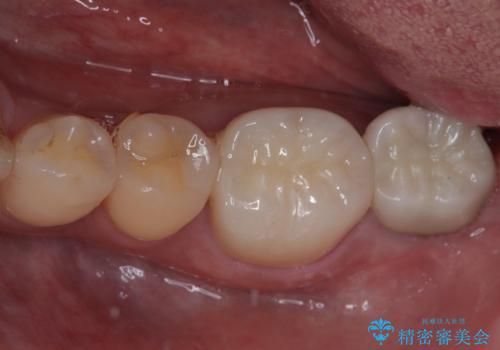

- 歯肉が退縮したためにクラウンの縁や歯根が見えてしまっていることを気にして来院された患者様です。

仮歯に変えた後にオールセラミッククラウンにて補綴することとしました。

治療前と比べてとても自然な前歯となり、患者様には大変満足していただきました。